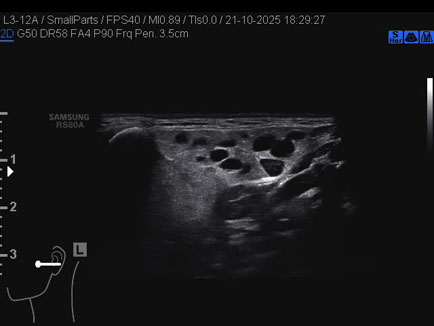

Ecografia del: 21/10/2025

Strumento: Samsung

Sonda: Lineare

Età Paziente: 50 anni

Commento all'esame: 50enne con stenosi del dotto di Stenone sn ed ectasia del dotto medesimo a dx.

Conclusioni: stenosi del dotto di Stenone sinistro (left Stensen's duct stenosis).